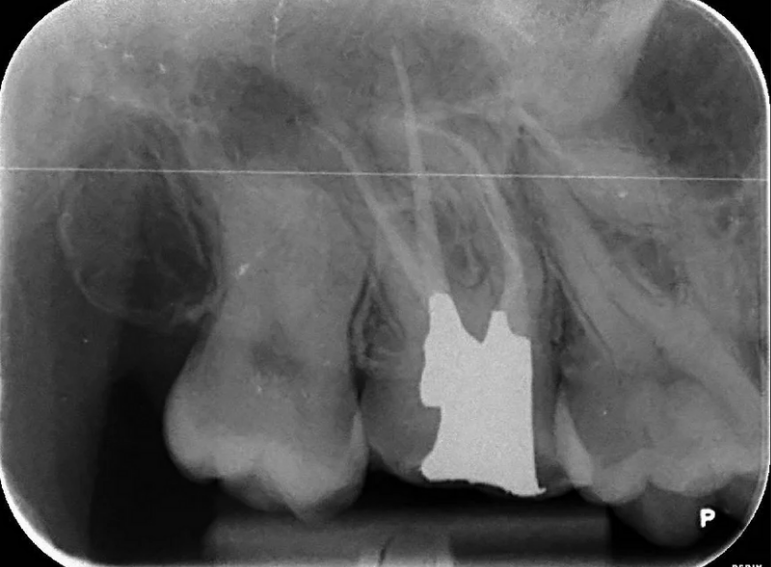

Separated instrument management on a sclerosed upper second molar.